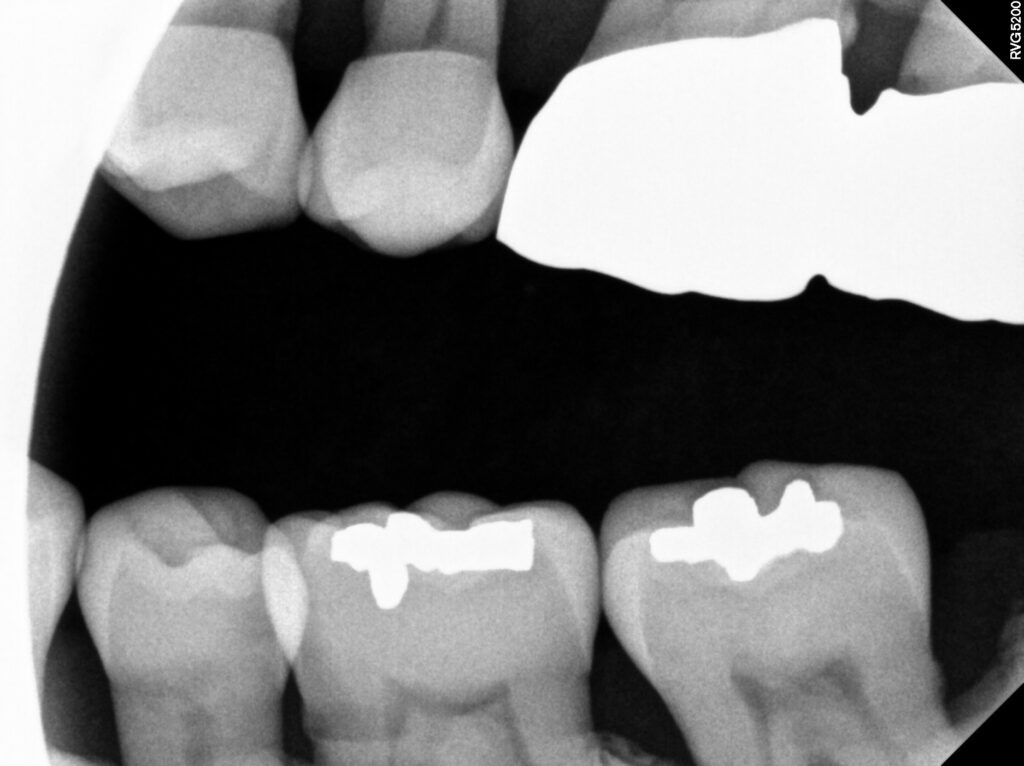

위쪽 작은 어금니 두개는 신경관이 보일 정도였지만

현재 증상이 없다고 하셔서 치수 복조 후 레진,

아래 송곳니는 신경치료 후 레진으로

수복할 수 있도록 계획하였습니다.